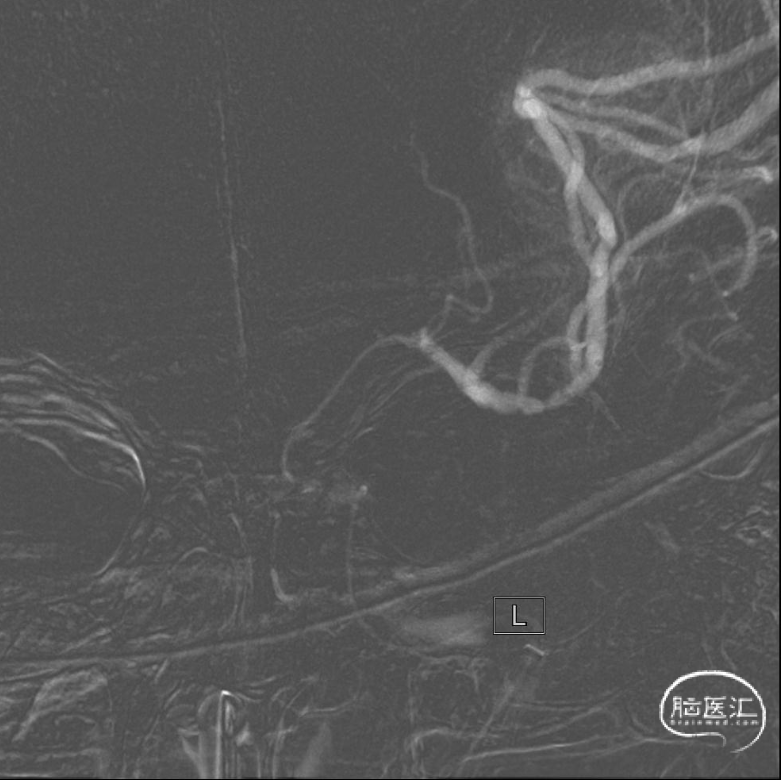

21:10 DWI+MRA序列:MRI显示左侧半卵圆中心、基底节区呈高信号,MRA显示左侧颈内动脉闭塞。

绿道核磁脑梗死一站式检查:MRI显示左侧半卵圆中心、基底节区呈高信号,MRA显示左侧颈内动脉闭塞。

造影评估:L-ICA侧位造影示ICA末端、眼动脉以远闭塞,未见明显颅内代偿情况。行同侧后循环造影:后交通未开放,通过脑膜支向前循环少量代偿。根据造影结果提示并结合患者房颤病史,考虑此次发病机制:栓塞。

本病例是一例左侧颈内动脉末段的大负荷血栓病例,左侧颈动脉DSA造影可见眼动脉呈“杯口”状的闭塞残端,结合房颤病史,考虑为心源性栓塞。术者采用了Catalyst 6路内支持导管,结合Trevo ProVue 6*25取栓支架,采用抽拉结合技术,快速开通了闭塞血管,实现3级再通,病人症状迅速改善。术者取栓策略选择合理,操作娴熟。

1.核心梗死与侧支循环情况。本病例术前DWI检查显示核心梗死体积不大。MRA可见前交通动脉开放,大脑后动脉亦有软膜支代偿,提示有较好的侧支循环。